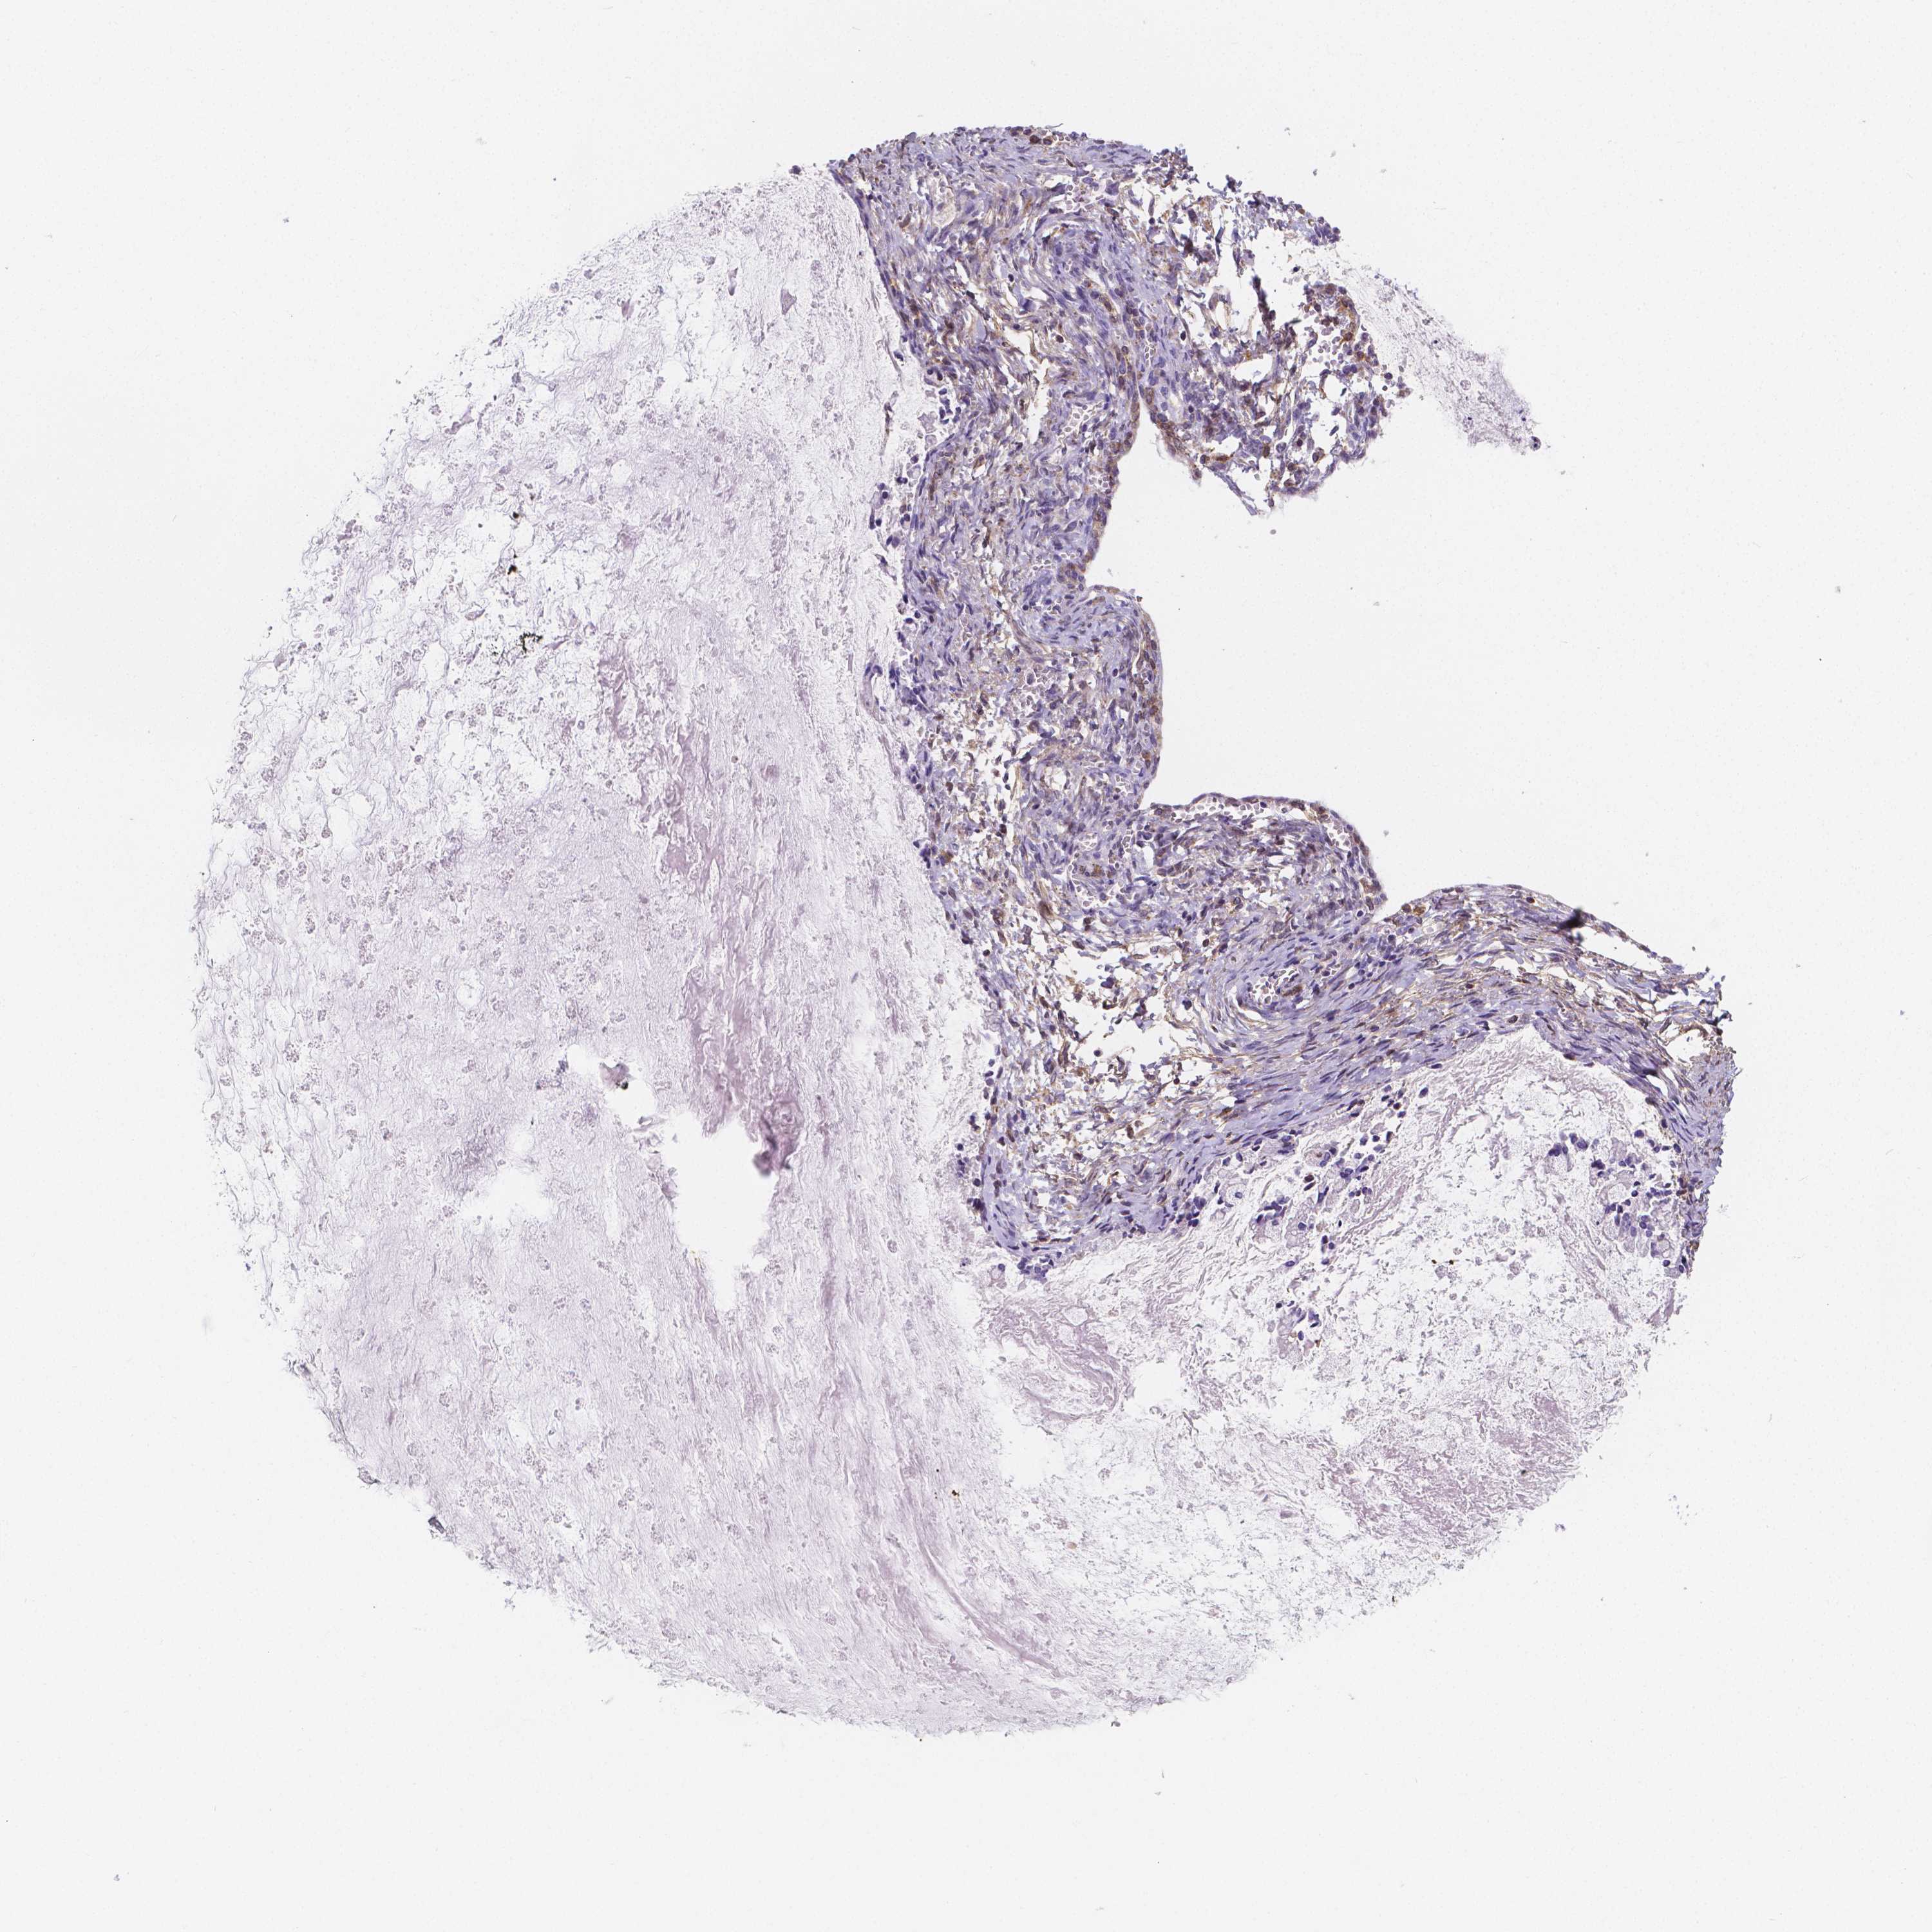

OVARIAN CANCER - Protein expressioni

A mouse-over function shows sample information and annotation data. Click on an image to view it in a full screen mode. Samples can be filtered based on level of antibody staining by selecting one or several of the following categories: high, medium, low and not detected. The assay and annotation is described here.

Note that samples used for immunohistochemistry by the Human Protein Atlas do not correspond to samples in the TCGA dataset.

Antibody stainingi

Antibody staining in the annotated cell types in the current human tissue is reported as not detected, low, medium, or high, based on conventional immunohistochemistry profiling in selected tissues. This score is based on the combination of the staining intensity and fraction of stained cells.

Each image is clickable and will lead to virtual microscopy that enables deeper exploration of all samples and also displays staining intensity scores, fraction scores and subcellular localization as well as patient and tissue information for each sample.

Antibody HPA044371

Staining

High

Medium

Low

Not detected

Intensity

Strong

Moderate

Weak

Negative

Quantity

>75%

75%-25%

<25%

None

Location

Nuclear

Cytoplasmic/membranous

Cytoplasmic/membranous,nuclear

Cystadenocarcinoma, serous, NOS

Cystadenocarcinoma, mucinous, NOS

Carcinoma, endometroid